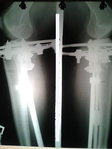

Рентген контроль в 1,5 месяца после снятия аппаратов.

сращение отличное, разрешены постепенно возрастающие нагрузки и каблуки.